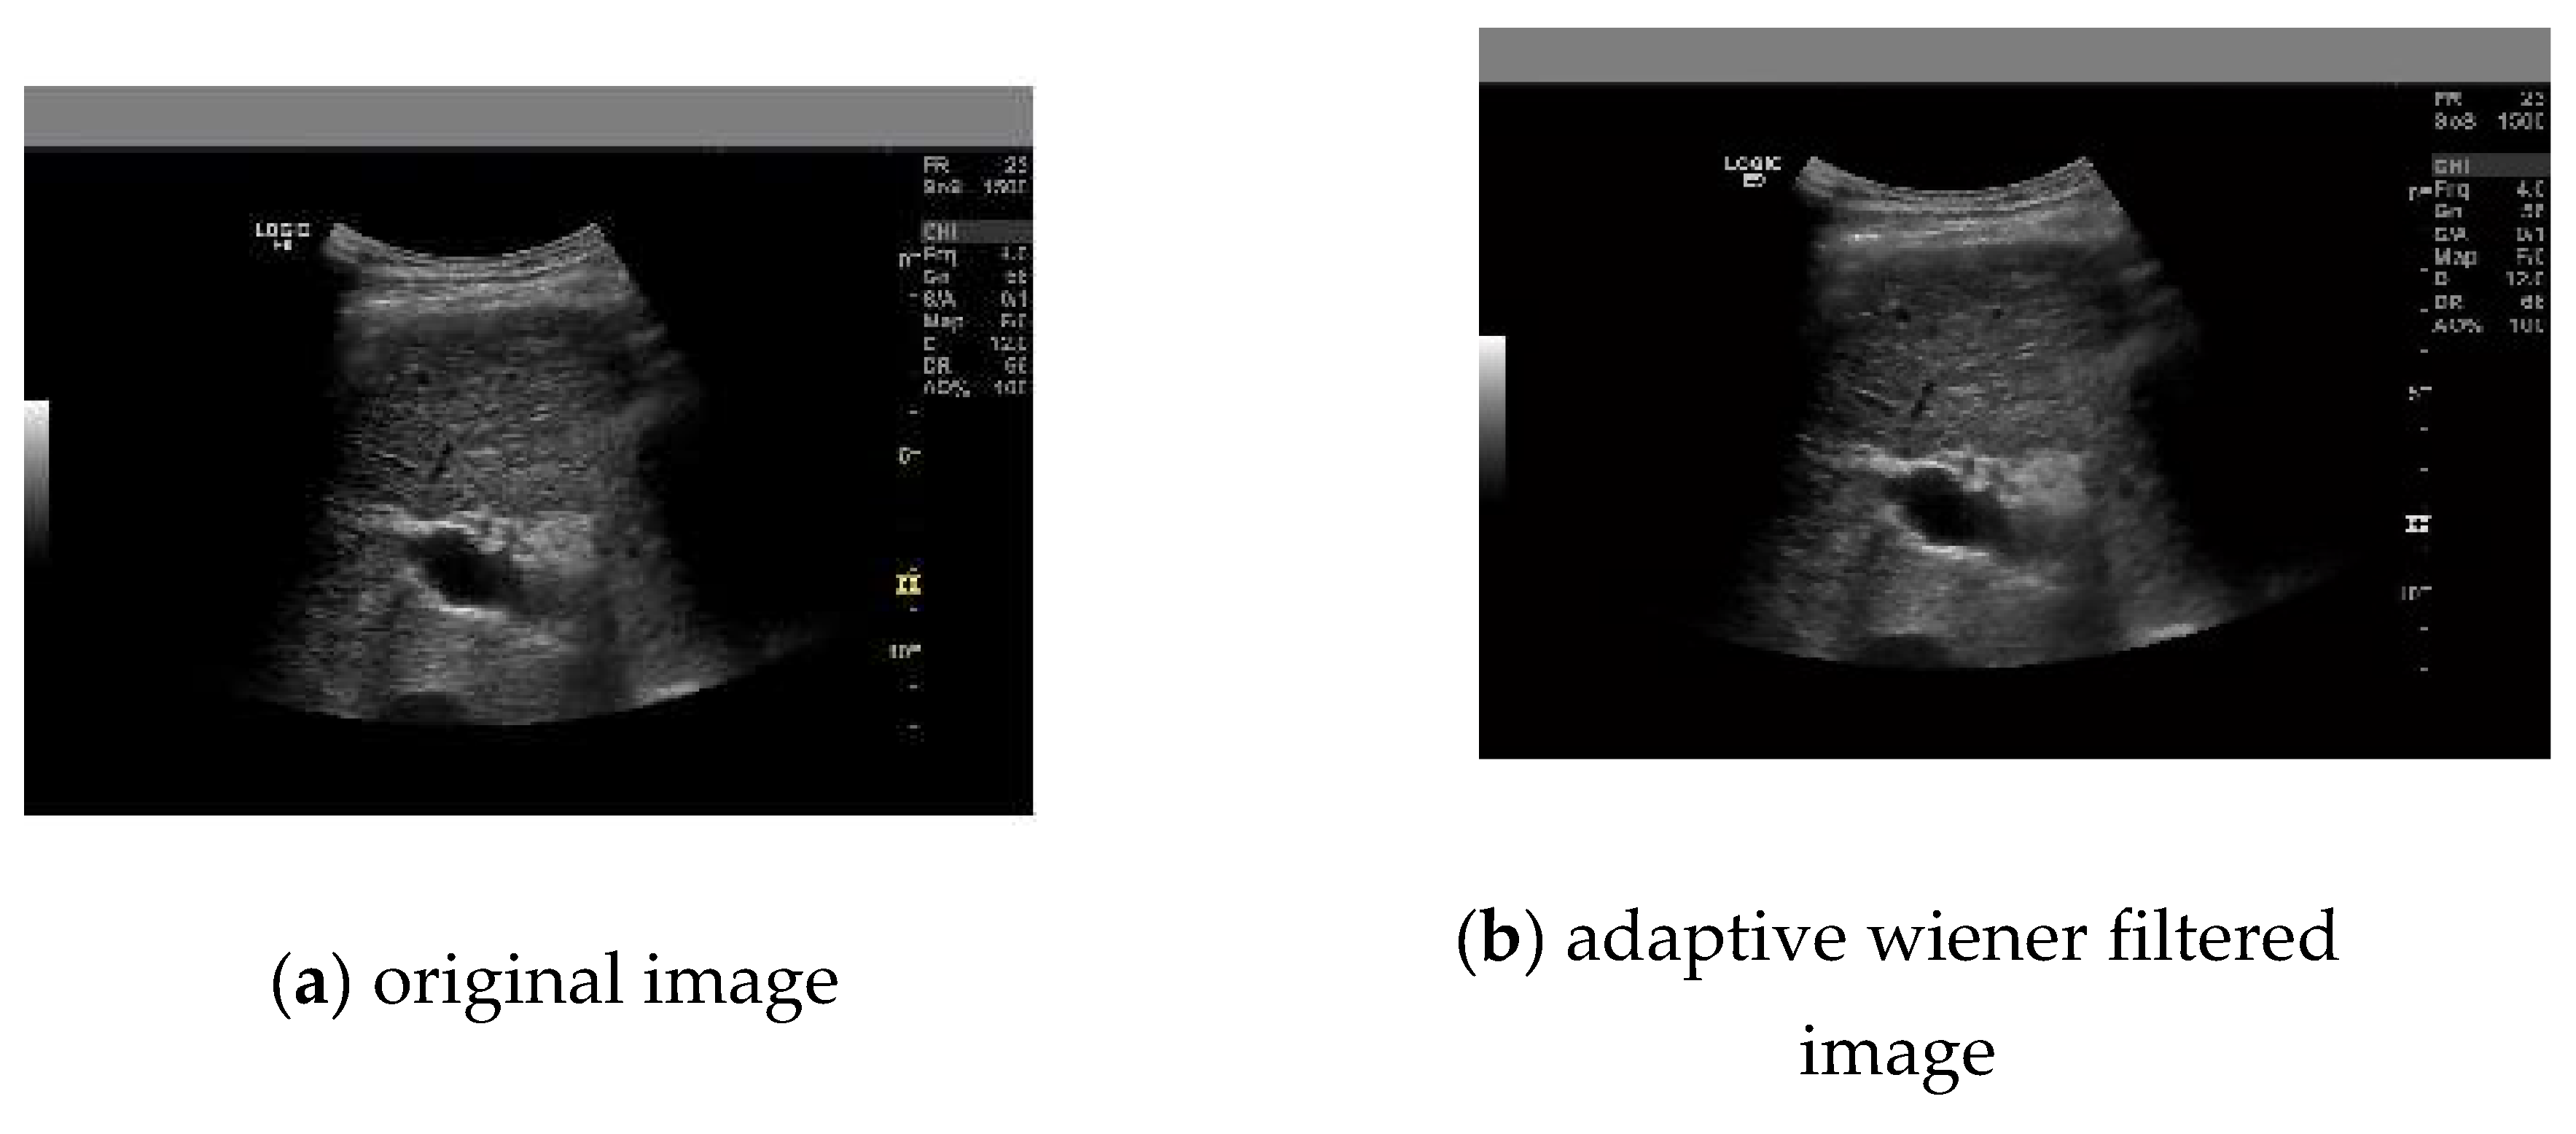

- Fahnun, Budi &Mutiara, Achmad&Prasetyo, Eri& Harlan, Johan & Abdullah, Apriyadi&Latief, Muhammad. (2018). Filtering Techniques for Noise Reduction in Liver Ultrasound Images. 261-266. 10.1109/EIConCIT.2018.8878547.

- Wu, F.; Yang, W.; Xiao, L.; Zhu, J. Adaptive Wiener Filter and Natural Noise to Eliminate Adversarial Perturbation. Electronics 2020, 9, 1634. [Google Scholar] [CrossRef]